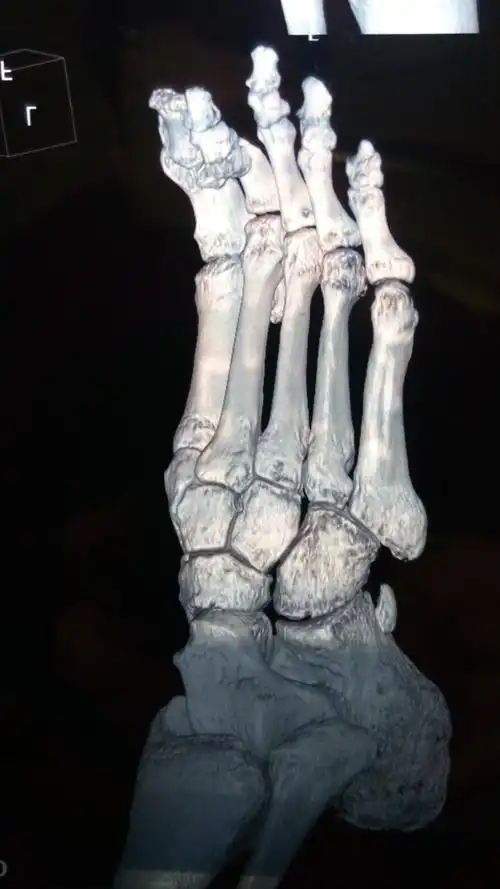

大脚骨病的微创手术

图片尺寸960x1280